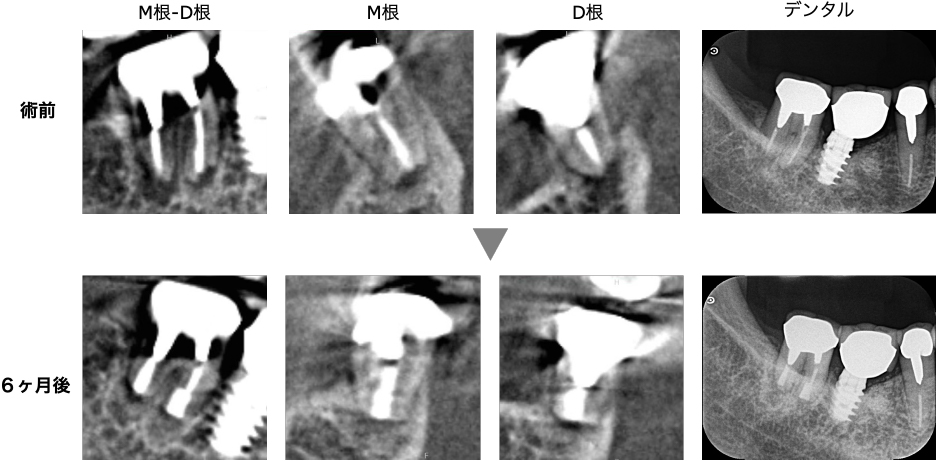

術前-術後の比較

術前と術後のレントゲン・CT画像を比較すると、根の先の黒い影(根尖部の透過像)の縮小傾向を認め、経過良好といえます。

D根(遠心根)のみわずかに黒い影は残っていますが、治る方向へ進んでおり、時間経過とともに完全に治癒すると考えられます。

症状もないため、このまま継続的に経過観察を続ける予定です。